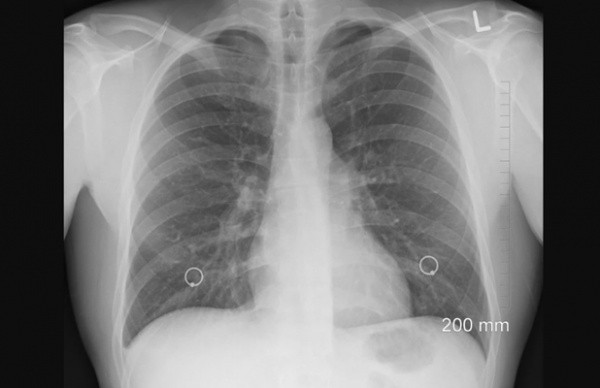

В общей сложности в инфекционных стационарах лечатся 272 человека, у 268 – диагностирована пневмония. 127 человек имеют лабораторно подтвержденную коронавирусную инфекцию. Течение болезни у большинства (214 человек) - средней степени тяжести. 58 человека находятся в тяжелом состоянии. К аппаратам ИВЛ подключены 16 пациентов. 134 человека нуждаются в кислородной поддержке.